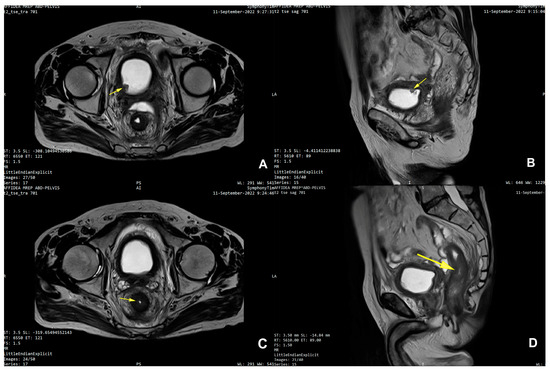

3. Detailed Case Description

| 25 | Present Case (2025) | 64/M | UCC G3/conventional and signet ring cell | GATA3, CK 20/CK5/6, P63, CDX | colonoscopy, rectal EUS TCB | rectal tenesmus, transit disorders (constipation/small volume diarrhea), moderate dysuria | DISTAL MEDIUM R |

| 25. | Present Case (2025) | 64/M | 0 | NO | Colostomy, NEOADJ CHT GC, RT | 15 M/D | T2N0M0 |